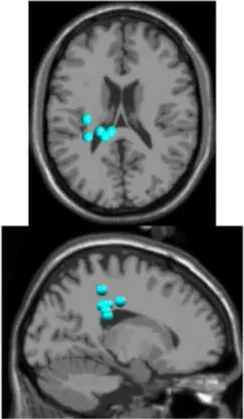

As expected the average treadmill belt velocity was more variable during active treadmill walking, regardless of command speed (Figure 3A). Average pelvis velocity in the sagittal plane was similar for the slow and fast walking commands, indicating the participants were able to match the desired treadmill command speed accurately during the steady walking tasks (Figure 3B). The k-means clustering resulted in seven spatially distinct clusters of electrocortical dipole sources, plus one additional outlier cluster (Table 1). We identified the Brodmann areas represented within each cluster from the Talairach atlas (Lancaster et al., 2000); dipoles were located within ±3 mm cube range of 14 Brodmann areas across the seven clusters. We performed spectral and time-frequency analysis on 6/7 clusters with the RPM cluster omitted because it did not contain ICs from a majority of the participants.

Table 1

| Posterior parietal | Left motor | Right motor | Left premotor | Right premotora | Anterior cingulate | Prefrontal | |

|---|---|---|---|---|---|---|---|

![]() | ![]() | ![]() | ![]() | ![]() | ![]() | ![]() | |

| Number of subjects | 7 | 5 | 5 | 5 | 3 | 5 | 5 |

| Number of ICs | 9 | 5 | 5 | 5 | 4 | 5 | 5 |

| Brodmann areasb | 5, 7, 31 | 3, 4, 31 | 1, 3, 4, 6 | 6, 8, 24 | 6, 24 | 24, 32, 33 | 9, 10, 32, 46 |

Clusters of dipolar sources fit to independent components.

aThe RPM cluster was omitted from analysis because it did not contain ICs from a majority of the subjects.

bBrodmann Areas reflect those found within a ±3 mm search range of all individual dipoles within a cluster.